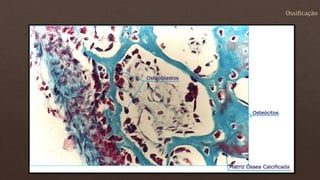

O documento lista os números de vértebras de diferentes animais e descreve as células e estruturas ósseas, incluindo osteoblastos, osteoclastos, matriz óssea mineralizada e não mineralizada. Também menciona a diferenciação de células mesenquimatosas em osteoblastos que secretam a matriz óssea.